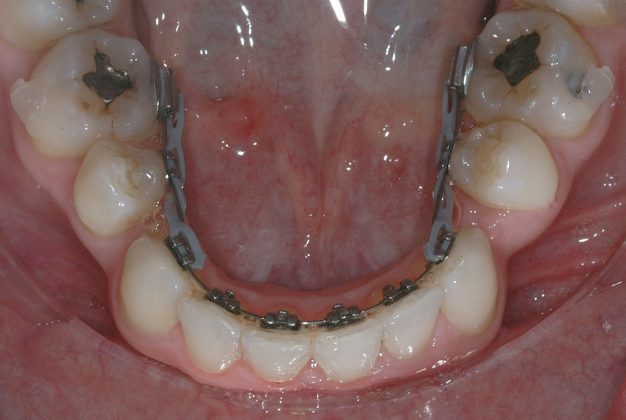

Per la chiusura dello spazio all’arcata inferiore, dopo la preliminare fase di allineamento e livellamento2, con la stessa sequenza iniziale di archi (.014” e poi .016” Nichel-Titanio), è stato temporaneamente applicato un sistema di ancoraggio ausiliario vestibolare, mediante fibre rinforzate, bondate sulla superficie vestibolare di 3.5, 3.6, 3.7 (Figura 4).

Al termine del trattamento ortodontico, che ha richiesto 24 mesi di terapia, è stata applicata una contenzione fissa3 all’arcata inferiore mediante filo multi-intrecciato coassiale .0195” esteso da 4.4 a 3.5 al fine non solo di stabilizzare il risultato sia sul piano orizzontale sia verticale, ma soprattutto per prevenire adeguatamente l’affollamento dentale terziario (Figure 9a-e).